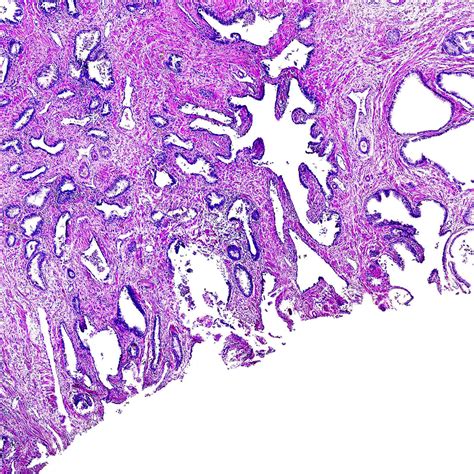

Observations when prostate cancer is suspected, tissue biopsy remains the standard of care for diagnosis.